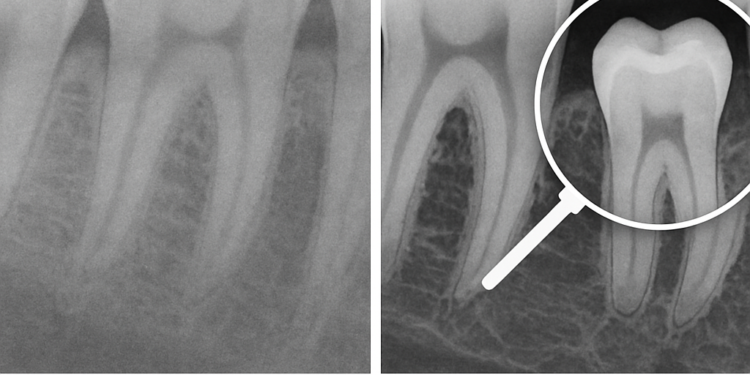

Uno de los pilares de este enfoque es el diagnóstico por imagen. La radiografía panorámica digital, por ejemplo, sigue siendo una herramienta muy utilizada para la primera valoración porque permite observar de manera global dientes, hueso y estructuras relevantes. En su versión digital, facilita la visualización, el almacenamiento y la comunicación clínica. Para pacientes que quieren informarse antes de su cita, La Clínica Dental publicó una guía práctica sobre el tema: https://laclinicadental.org/rayos-x-panoramicos-digitales-vs-convencionales-beneficios-y-como-funcionan/.